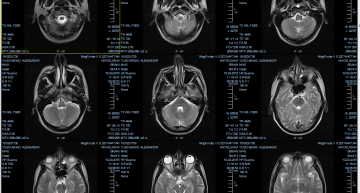

Здравствуйте! Прошу помогите. У моей мамы Семёновой Галины Адольфовны- 70 лет (1945 год рождения)- дома 23 ноября случился первый приступ инсульта . Положили в больницу - Молодечрненская городская больница- неврологическое тяжёлое отделение. Отнялась только правая рука. Тогда сделали КТ- нам -детям ,заведующая - Людмила Михайловна сказала иесульт средней тяжести, доброкачественное новообразование. Ничего насчёт опухоли делать не нужно- сказали. На КТ показала доброкачественное новообразование в голове. В тот момент через несколько дней на голову спящей мамы в 10 часов вечера - на лицо упала с потолка штукатурка -то есть некоторая часть . Это привело к отёку около глаза -огромный синяк, большая царапина , потеряла много крови. И рана на губе. Заведующая словами извинялась. И маму сразу на 3 дня перевели в палату интенсивной терапии. Конечно раны зажили, а испуг получила огромный, после такого и речь ослабилась. Продержали её 22 дняв больнице и выписали домой. Далеее уже дома через 2-3 недели ей стало хуже. Вызвали скорую -приехал старый доктор , по его словам всё будет нормально, сделали укол в вену и уехал. На следующий день 20 декабря в воскресенье вызвали скорую, мы уговорили врача скорой , завезли в больницу. Положили в районную больницу -неврологическое отделение-Молодечно. Сделали КТ 21 декабря- у них не получилось нам сказали. 22 декабря ещё сделали КТ. А 23 декабря на врач сказала , что у неё опухоль злокачественная в голове и от этого у неё отнимается правая сторона, уже лёжа в больнице , сейчас она не чувствует правой стороны. Можно ли вызвать нейрохирурга срочно в Молодечно и сделать операцию, удалить опухоль? И могло ли падение с потолка спровоцировать развитие злокачественной опухоли за 2-3,5 недели ? Или нам самим ехать в Минск на консультацию, куда позвонить , куда подъехать? Пожалуйста помогите. С уважением Лариса, 43 года, Молодечно, +375292723227, +375256982649. Почту электронную скиньте- я , Лариса , вышлю последнее КТ мозга мамы.